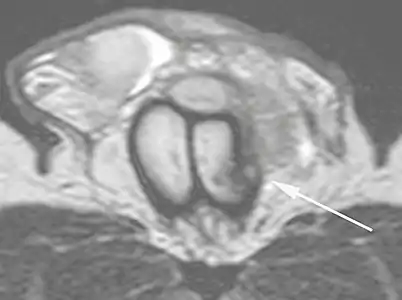

In the ultrasound examination, a lesion of the tunica albuginea presents as an interruption in (loss of continuity of) the echoic line representing it (Figure 4). Small, moderate, or broad hematomas demonstrate the extent of that discontinuity. Intracavernous hematomas, sometimes without the presence of a tunica albuginea fracture, can be observed when there is a lesion of the smooth muscle of the trabeculae surrounding the sinusoid spaces or the subtunical venular plexus.[2]

Figure 4 A: Ultrasound of the penis, right lateral view. Longitudinal section showing rupture of the tunica albuginea with an adjacent 1.92 cm hematoma (between calipers), due to trauma.[2]

B: Axial T2-weighted turbo spin-echo magnetic resonance imaging scan showing left-sided discontinuity of the tunica albuginea (arrow), secondary to fracture.[2]